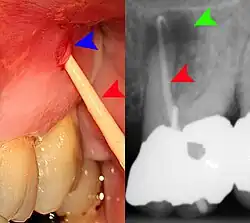

- Radiographs utilized to find dental caries and bone loss laterally or at the apex.

Gutta-percha point indicating abscess origin